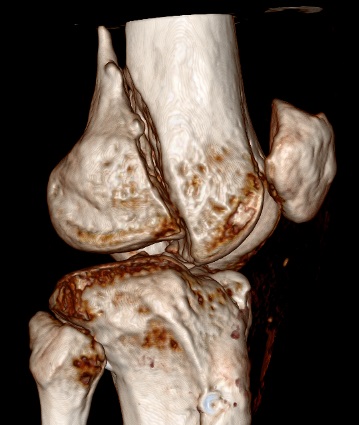

Диагностическая ошибка происходит, когда игнорируется правила обследования внутрисуставных переломов. Вместо полного обследования, включая КТ, ограничиваются рентгенограммой, и то в одной проекции!

Nork et al, J Orthop Trauma, 87:564, 2005 доложили, что над- и чрезмыщелковые переломы бедра в 38% имеют линию перелома в корональной плоскости!

Спасибо большое за советы! Добавляю некоторые КТ снимки. Перелом коллеги не диагностировали, видимо, расценив костную травму как повреждение задне-латерального комплекса коленного сустава. Отпишусь по результату выполненной операции.